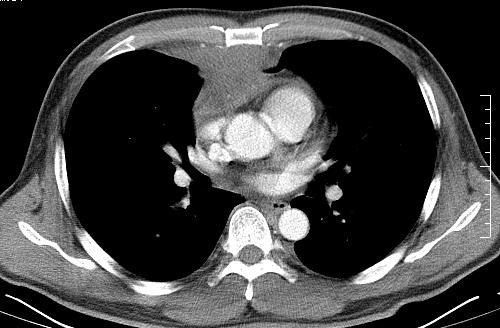

男   40   反复腹痛入院行彩超检查示胸骨右缘4、5肋间不均质回声团

淋巴瘤:前纵隔可见多组肿大的淋巴结,部分融合,有液化坏死

上区却那么有点象占位,胸腺瘤不太象,一点强化也没有,淋巴瘤气管前上腔静后却很干净,下区也点象纵隔积血征,

莲蓬籽征  考虑淋巴瘤